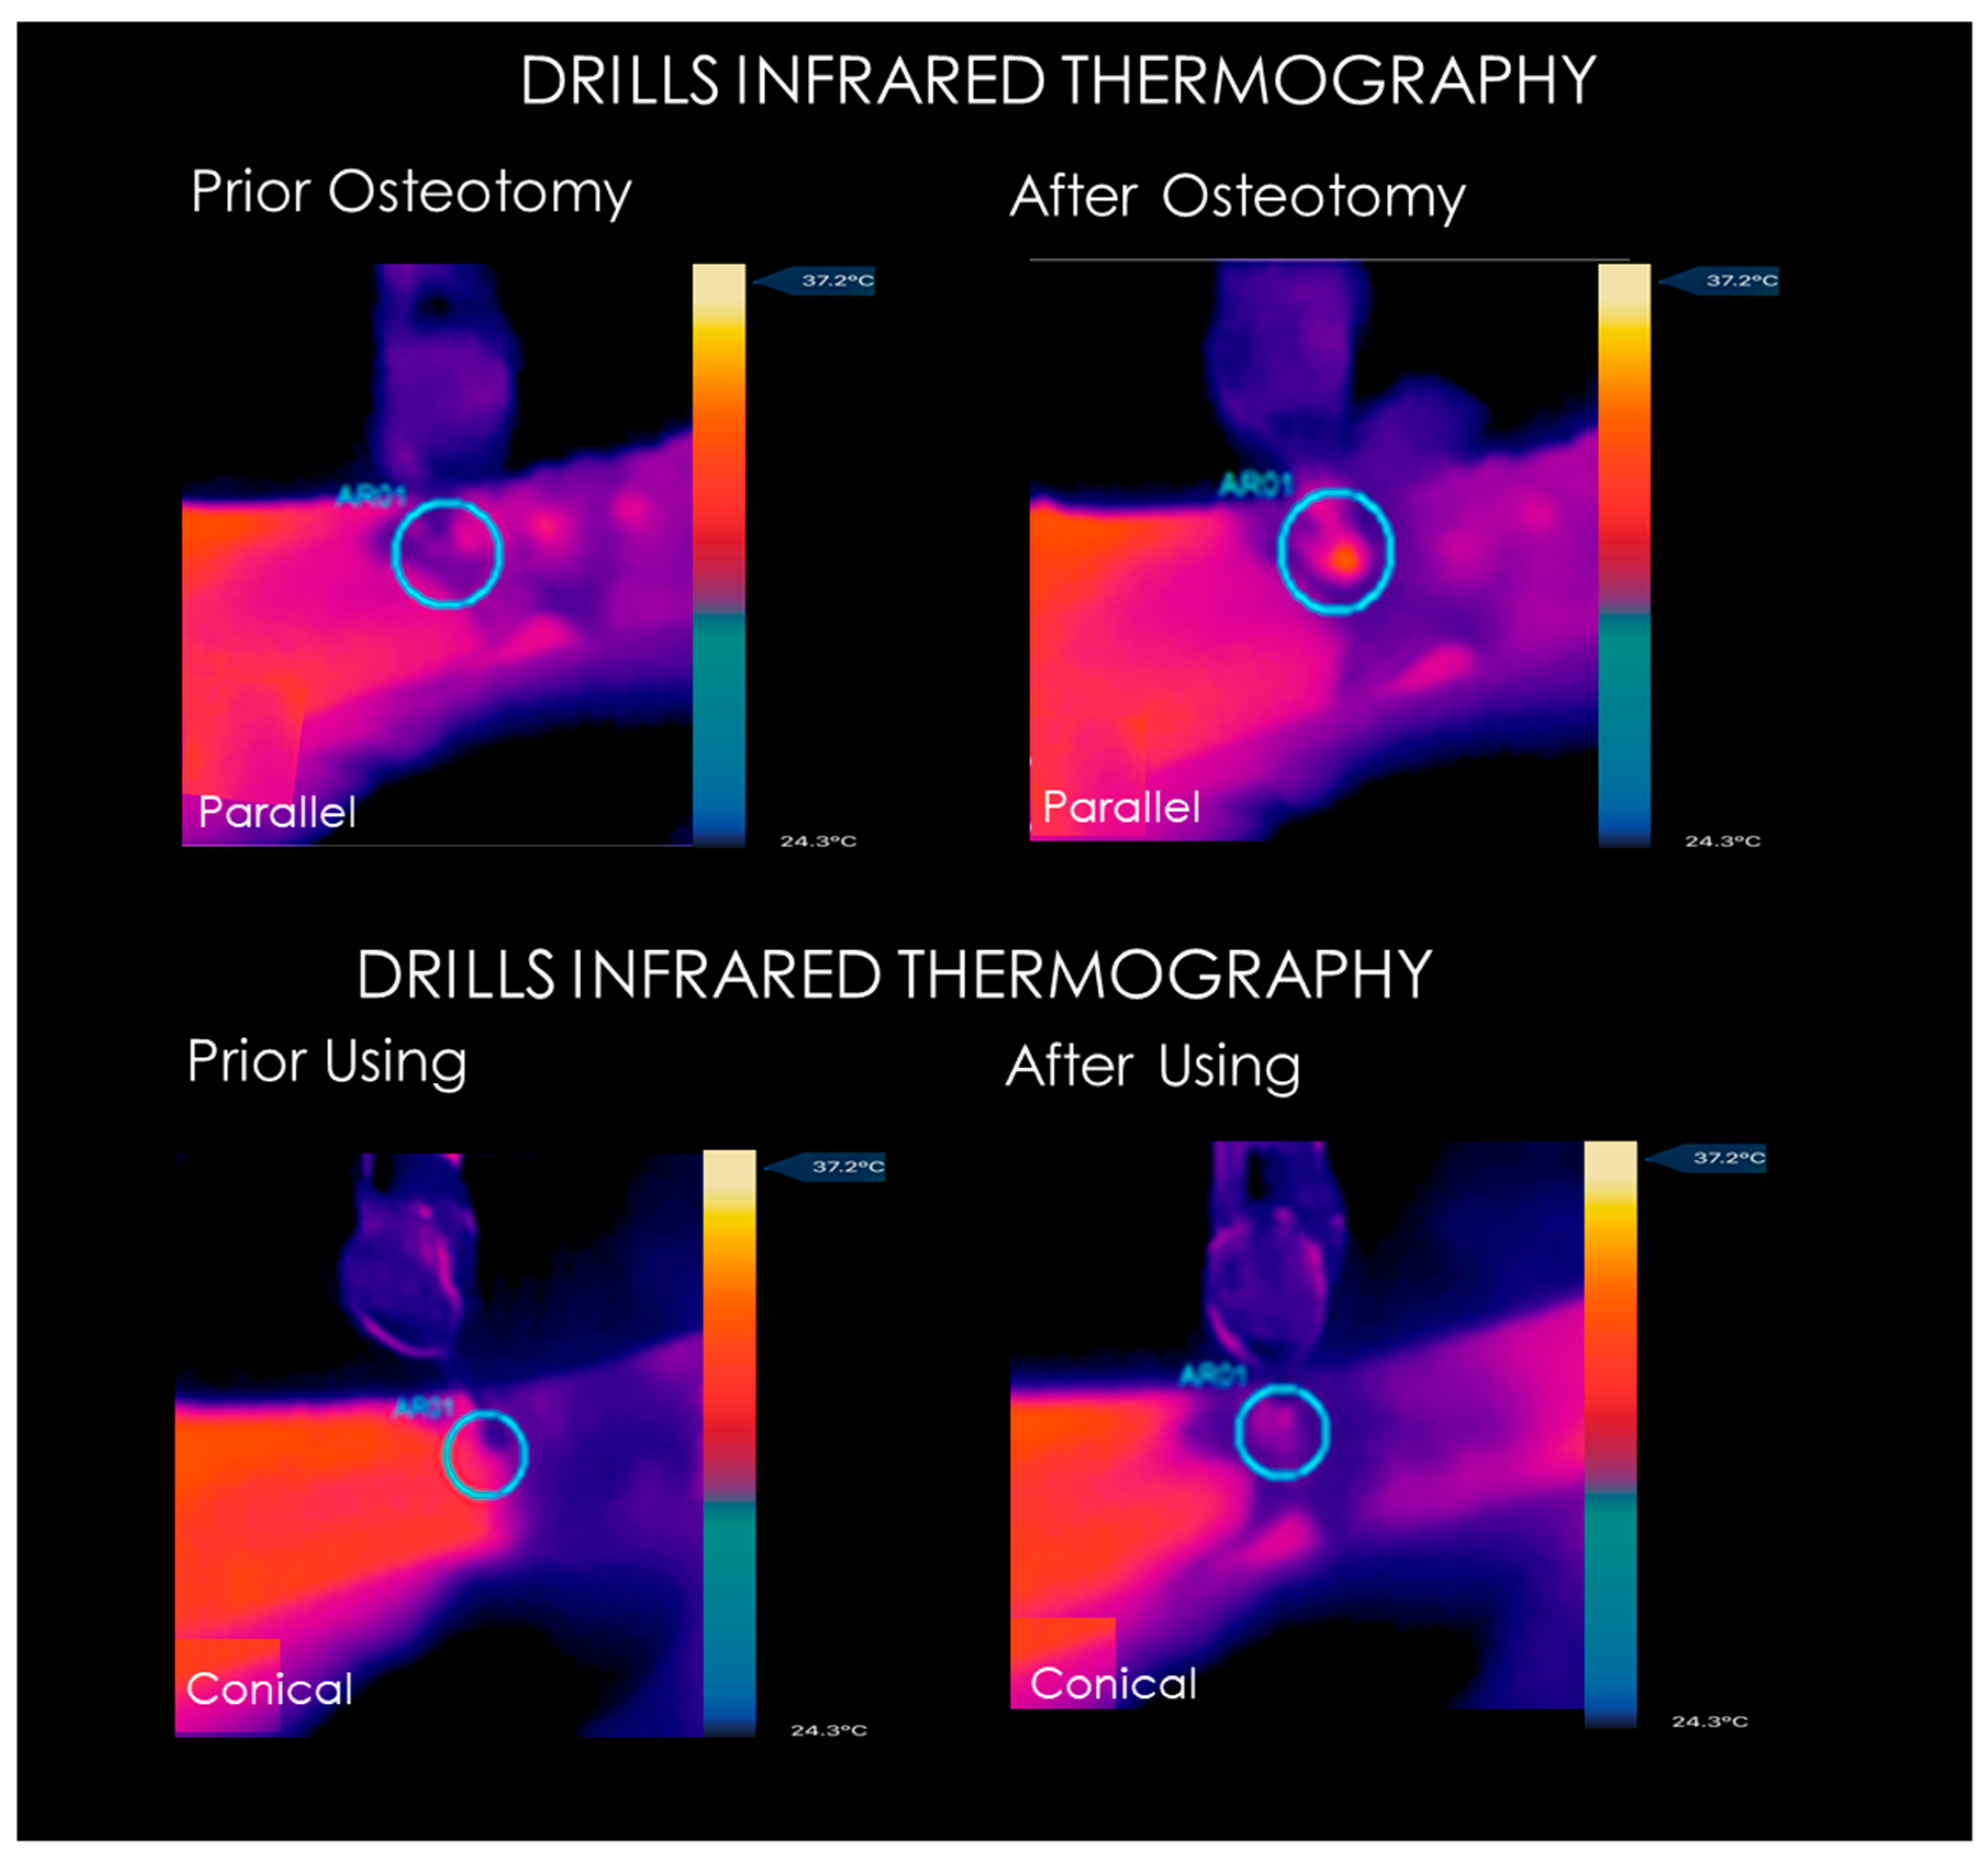

2.2. Infrared Thermographic Measurements

3.1. Infrared Thermography Measurements

| Drill Bone Temperature (°C). | Baseline | FGR3710 | FGR5513 | FFC3710 | FFC5513 | DRP200 | DRP450 | CTK425 |

|---|---|---|---|---|---|---|---|---|

| 1st osteotomy | 37.0 ± 0.10 °C | 38.6 ± 0.66 | 40.96 ± 0.59 | 39.01 ± 0.51 | 41.12 ± 0.47 | 38.59 ± 0.73 | 39.37 ± 0.63 | 39.25 ± 0.55 |

| After 30th osteotomy | 37.0 ± 0.13 °C | 39.01 ± 0.56 | 41.83 ± 0.56 | 39.37 ± 1.12 | 41.97 ± 0.51 | 39.01 ± 0.56 | 39.89 ± 0.71 | 39.71 ± 0.63 |

| p-value | / | * p > 0.05 | * p > 0.05 | * p > 0.05 | * p > 0.05 | * p > 0.05 | * p > 0.05 | * p > 0.05 |

| TapperBone Temperature (°C) | Baseline | MKN3710 | MKN3711 | MKN3713 | MKN3714 | MSL5510 | MSL5511 | MSL5513 |

|---|---|---|---|---|---|---|---|---|

| 1st osteotomy | 37.0 ± 0.14 °C | 38.1 ± 0.5 | 38.3 ± 0.47 | 38.3 ± 0.50 | 38.5 ± 0.45 | 38.2 ± 0.46 | 38.4 ± 0.57 | 38. 8± 0.66 |

| After 30th osteotomy | 37.0 ± 0.12 °C | 38.1 ± 0.5 | 38.3 ± 0.47 | 38.3 ± 0.50 | 38.5 ± 0.45 | 38.2 ± 0.46 | 38.4 ± 0.57 | 38.8 ± 0.66 |

| p-value | / | * p > 0.05 | * p > 0.05 | * p > 0.05 | * p > 0.05 | * p > 0.05 | * p > 0.05 | * p > 0.05 |